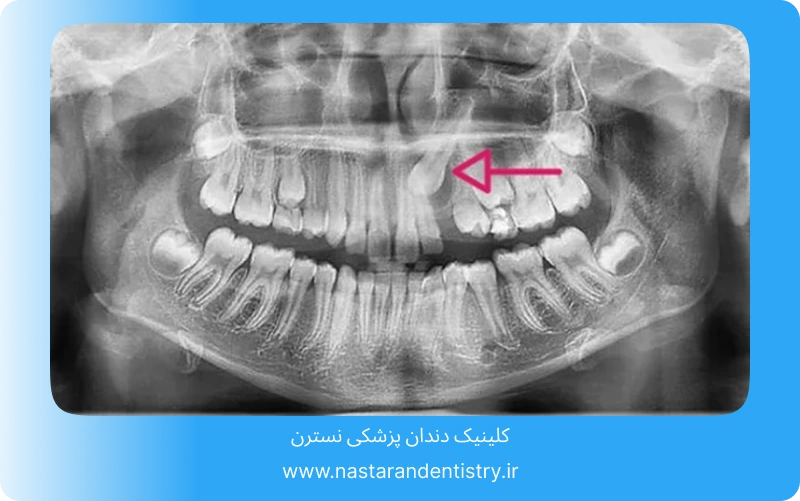

یکی از مهمترین عواملی که در جواب به سوال جراحی دندان نیش نهفته چقدر طول میکشد تاثیر گذار است ، موقعیت دندان نیش در فک است. اگر دندان نیش در عمق استخوان قرار گرفته باشد و یا در جهت نامناسبی رشد کرده باشد، جراحی پیچیدهتر و زمانبرتر خواهد بود. در مواردی که دندان نیش نزدیک به سطح لثه باشد، جراحی سادهتر و سریعتر انجام میشود.

دندان نیش نهفته به دندانی گفته میشود که به دلایل مختلفی مانند کمبود فضا در فک، موقعیت نامناسب دندان یا اختلالات رشد، نتوانسته است به موقع از لثه بیرون بزند و در داخل استخوان فک باقی مانده است. این دندانها میتوانند به صورت کامل یا جزئی در استخوان مدفون باشند.